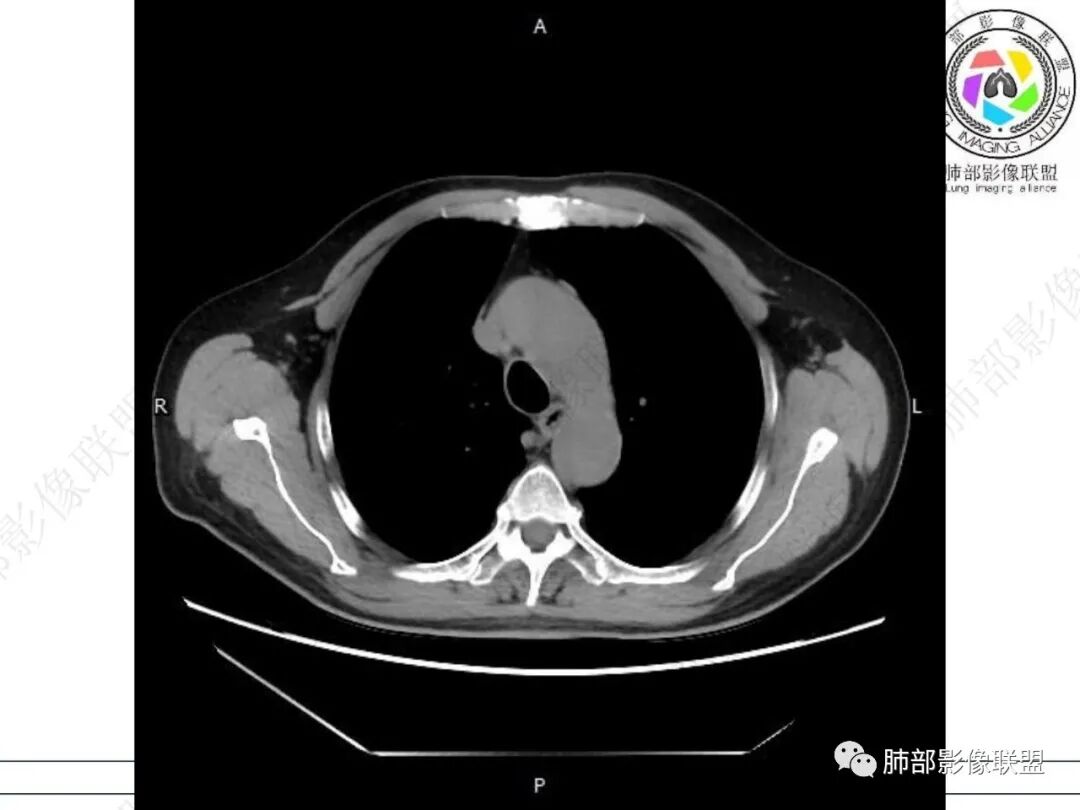

右肺下叶沿肺叶肺段分布斑片、条片状影,以下叶背段为显,边缘模糊,内可见支气管走行,局部支气管管壁增厚,右侧胸腔少量积液。纵隔隆突下可见不均匀软组织密度影,与周围结构分界不清,内见气体密度影,与食管及相邻右肺支气管之间未显示通道。邻近食管下段壁明显不规则增厚,增强后食管管壁明显不均匀强化,可见线样强化的连续完整粘膜影。

3.综合分析:

右肺下叶片影,气道相关,符合感染性病变。纵隔隆突下软组织密度影,异常气体影,长病程,起病缓慢,提示存在气管或食管瘘。食管镜未见明显新生物形成,临床未提供进食或饮水呛咳临床表现,综合分析应该考虑支气管瘘的形成。